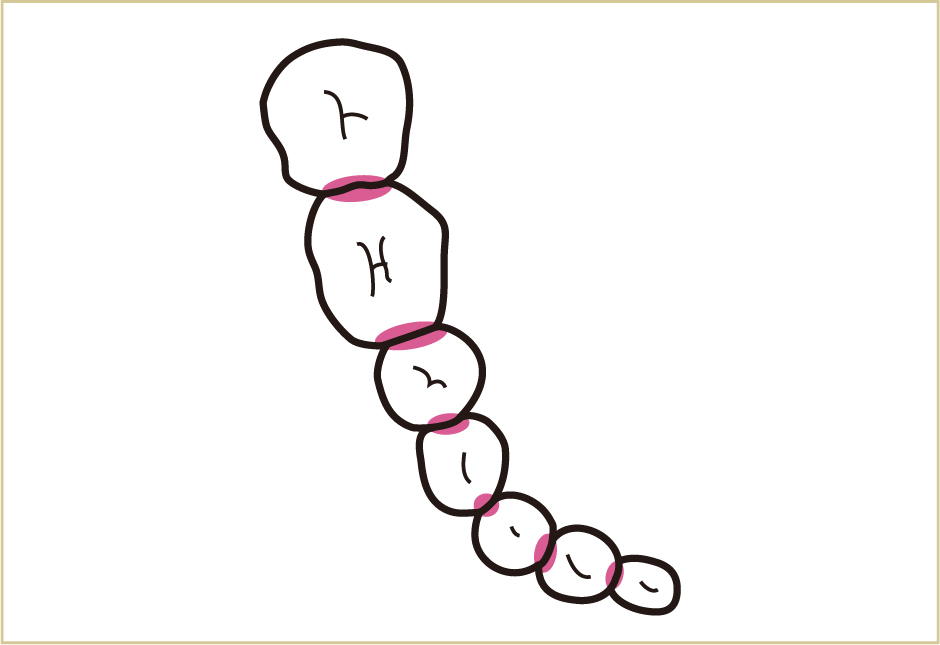

歯と歯肉の溝にみがき残しができる。

みがき残しの中に唾液中の細菌が入り込む。

細菌は、酸や毒素など、いろいろな代謝産物を周囲にまきちらす。毒素は歯肉に対して毒の働きをし、口臭の原因にもなる。また酸で歯が溶けて虫歯になる。

細菌の出す毒が歯肉に触れたり侵入したりすることで、歯肉が腫れてふくらみ、血が出やすくなって炎症が生じる。

腫れた歯肉は、ますます汚れがつきやすく、みがき残しができやすい形になっていき、より多くの細菌による毒素が歯肉に影響を与えるようになる。

いつも同じ所にみがき残しがあると、その表面に唾液中のカルシウムなどが沈着して硬くなってしまう(これが歯石)。

みがき残しが何層にも降り積もると、初めについたみがき残しは空気が触れにくい環境になり、より毒性の強い菌(歯周病原菌、嫌気性細菌)が増えてくる。

表面が歯石でガードされているため、ブラッシングしても汚れはとれない。空気が触れにくい深部には、より毒性の強い菌が増える。そのため歯肉に多くの毒素が入り込み、歯と歯肉とのバリアが壊されていく。

さらに病状が進行すると、細菌による毒素は、歯肉だけでなく、歯を支える骨や歯根表面にまで悪影響を与える。その結果として、歯を支える骨が壊れていく。

歯周病とは、歯を支える骨を壊す病気である。